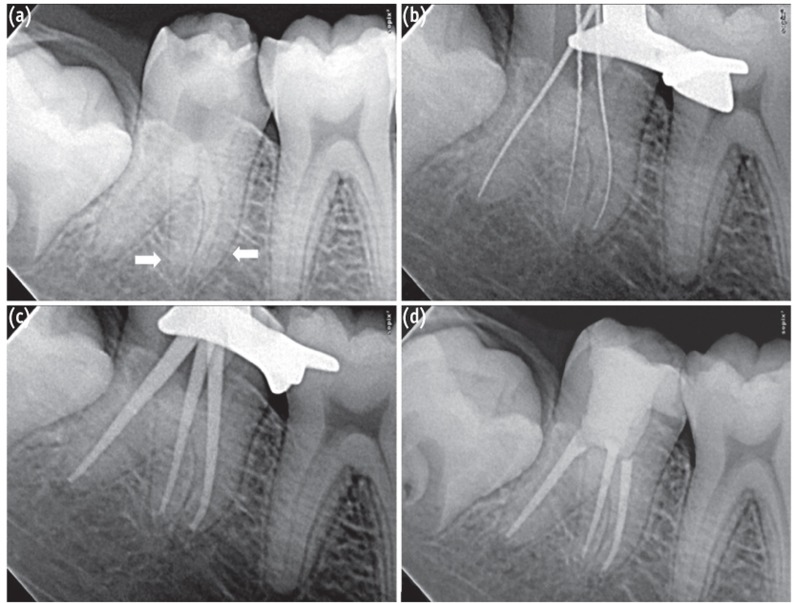

A 16-year old male patient presented to the Department of Conservative Dentistry and Endodontics with a chief complaint of pain in his lower right posterior region of mouth for one week. The patient revealed a history of mild intermittent pain for the past 2 months, which had increased in intensity since one week ago. The patient reported subjective symptoms of prolonged sensitivity to hot and cold food and drinks. The pain was spontaneous and aggravated particularly at night and required analgesic to get relief from pain. The medical history contained no abnormal data. Clinical examination revealed a deep carious lesion on the proximal surface of right mandibular second molar (tooth #47). Palpation and percussion test of the involved tooth did not reveal any tenderness. The tooth was not mobile and periodontal probing around the tooth was within physiological limits. Thermal testing of the involved tooth with heated gutta-percha (Dentsply Maillefer, Ballaigues, Switzerland) and cold spray (Roeko Endo-Frost, Coltène-Whaledent, Langenau, Germany) caused an intense lingering pain, whereas electronic pulp stimulation (Parkell Electronics Division, Farmingdale, NY, USA) caused an early response. The preoperative diagnostic radiograph showed carious lesion closely approximating the pulp with no signs of periapical changes (Figure 1a). From the clinical tests and radiographic findings, a diagnosis of symptomatic irreversible pulpitis was made and endodontic treatment was initiated.

Radiographic evaluation of the involved tooth revealed an unusual anatomical configuration suggesting the possibility of the presence of two mesial roots (Figure 1a). The mesial surface of the tooth was restored with composite resin (P60, 3M ESPE, St. Paul, MN, USA) after caries excavation to enable optimal isolation. The tooth was anesthetized using 1.8 mL 2% lidocaine with 1 : 200,000 epinephrine (Xylocaine, AstraZeneca Pharma India Ltd., Bangalore, India). Following rubber dam isolation, an endodontic access cavity was established. On inspection with a DG-16 endodontic explorer (Hu-Friedy, Chicago, IL, USA) under an operating microscope (Roslane Meditech, Haryana, India), the pulp chamber floor revealed three canal openings corresponding to the two mesial and one distal roots (Figure 2). The mesiobuccal, mesiolingual, and distal canal orifices were located in their regular locations at the angles in the floor-wall junction. Further inspection of the pulpal floor was done for search of other orifices that were absent. Coronal enlargement was done with a nickel-titanium (NiTi) ProTaper SX rotary file (Dentsply Maillefer) to improve the straight-line access. The pulp tissue was extirpated using barbed broaches (Dentsply Tulsa, Tulsa, OK, USA). The working length was initially determined with the help of an apex locator (Raypex5, VDW, Munich, Germany) and confirmed using radiographs taken at different horizontal angulations. The working length radiographs showed three independent root canals in three separated roots (Figure 1b). Cleaning and shaping was done using ProTaper NiTi rotary instruments (Dentsply Maillefer) along with ethylenediaminetetraacetic acid (Glyde File Prep, Dentsply Tulsa) using a crown-down technique. Irrigation was performed using 3% sodium hypochlorite solution (Cmident, Cmident, New Delhi, India). Afterwards, a closed dressing was given with a sterilized cotton pellet in the pulp chamber with access cavity restored with Cavit G (3M ESPE).

At the second appointment, the patient was asymptomatic. Temporary restoration was removed and irrigation was done with copious amounts of 3% sodium hypochlorite and 17% ethylenediaminetetraacetic acid (EDTA, Prevest Denpro Ltd., Jammu, India). The canals were finally flushed with sterile saline. Master cones were selected by placing cones corresponding to the size of the last finishing file used to the working length and was confirmed radiographically (Figure 1c). The canals were dried with absorbent points (ProTaper, Dentsply Maillefer) and obturation was carried out with ProTaper gutta-percha cones (Dentsply Maillefer) using AH Plus resin sealer (Dentsply Detrey GmbH, Konstanz, Germany). The tooth was then restored with a posterior composite resin core (P60, 3M ESPE). Final radiograph was taken to establish the quality of the obturation (Figure 1d). The patient remained asymptomatic during 1 year follow-up period.

Conventional intra-oral periapical radiographs has been the standard method for ascertaining varying morphology of the root and root canal system. If the outlines of the roots are unclear, the root canal shows sharp density changes or the apices cannot be well defined, then extra roots can be suspected.8 The use of a preoperative radiograph and an additional radiographic view from a 20-degree mesial or distal projection aids in the accurate detection of the periodontal ligament outlines, thus facilitating the interpretation of external root anatomy. Two periodontal ligament spaces on one side of a root and the periodontal ligament space crossing over roots are important observations that can indicate either the presence of 2 mesial roots, bifurcation of the mesial root, or a very broad faciolingually oriented mesial root.17 In our case, a 20-degree mesial angulation periapical radiograph of the right mandibular second molars revealed double periodontal ligament spaces in the mesial roots indicating the presence of an accessory mesial root (Figure 1a). CBCT investigations confirmed the existence 2 well separated mesial roots in which the level of bifurcation is at the coronal third (Figures 3a - 3d).

(a) Preoperative radiograph showing the external outlines of the two mesial roots (white arrows); (b) Working length radiograph showing three separate roots and root canals; (c) Master cone radiograph; (d) Post-obturation radiograph.

Figure 1 (a) Preoperative radiograph showing the external outlines of the two mesial roots (white arrows); (b) Working length radiograph showing three separate roots and root canals; (c) Master cone radiograph; (d) Post-obturation radiograph.